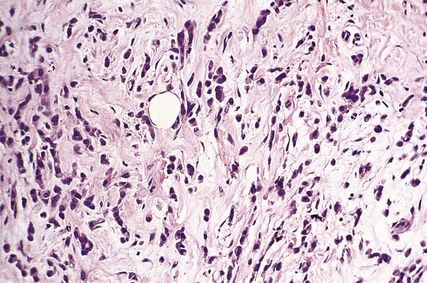

Histologically the cells are small and uniform and are dispersed singly, or in columns one cell wide (‘Indian files’; Fig. 18.23), in a dense stroma. Elastosis can be present. The cells infiltrate around pre-existing breast ducts and acini, rather than destroying them as occurs with invasive duct carcinomas. This method of infiltration may account for the occasional multifocal nature of the tumours. The cells in some carcinomas may appear signet-ring in shape due to the accumulation of mucin within an intracytoplasmic acinus, displacing the nucleus to one side. A characteristic feature of these tumours is that the cells lack the cell adhesion molecule E-cadherin, which may account for their pattern of spread. Residual lobular carcinoma in situ can sometimes be found in the invasive tumours.

image

Fig. 18.23 Infiltrating lobular carcinoma. Strands of single cells (Indian file) invade fibrous stroma.